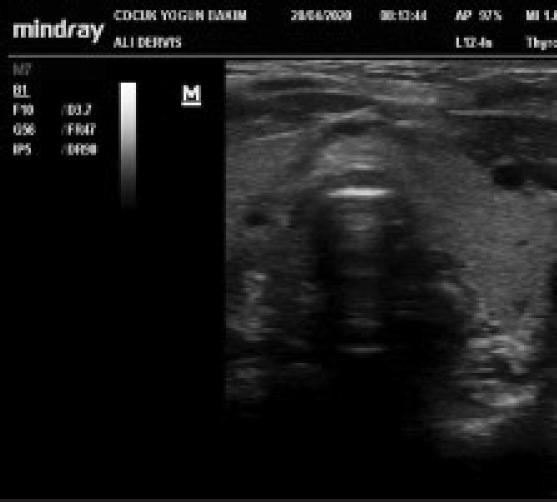

A new stethoscope for pediatric intensivists: Point-of-care ultrasound.

In recent years, the use of point-of-care ultrasound by non-radiologist physicians has become widespread. Especially for clinicians working in pediatric emergency departments and pediatric intensive care units, point-of-care ultrasound has almost become a part of physical examinations due to the rapid responses it offers to the problems of critically ill patients. Numerous studies revealed the important clinical benefits of point-of-care ultrasound use by pediatric intensive care providers. In this review, we aimed to give detailed information about different types of point-of-care ultrasound applications in pediatric intensive care units and wanted to draw attention to the increased use and clinical benefits of this noninvasive and radiation free technique.